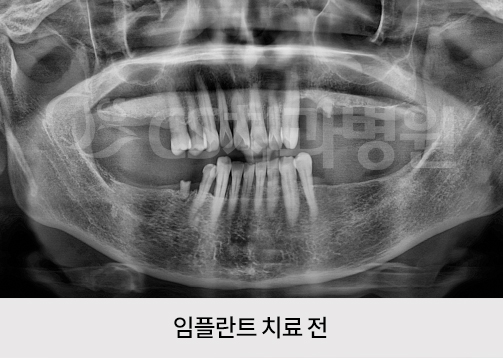

치료기간 : 2021.06.29 ~ 2022.01.17

*실제 본 원에서 치료를 받은 환자의 동의를 얻어 게재하였으며 무단 복제, 사용을 금합니다.

*부작용 고지 : 치료 후 감염, 염증, 연조직 합병증, 출혈, 감각이상 등의 부작용이 있을 수 있습니다.